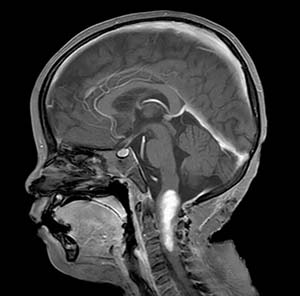

张玉琪教授对康复中的患者

阿什利(Ashley Gaille Tan Shiu)进行诊疗检查